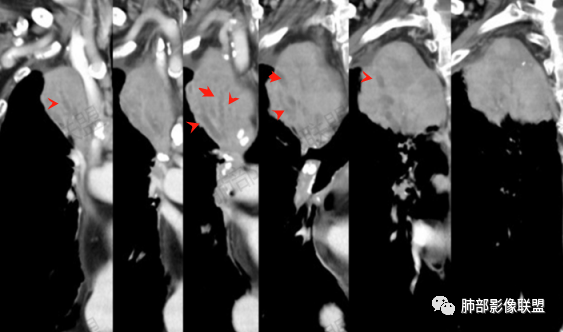

右肺体积小,提示既往结核

背段支气管周围增厚伴钙化,符合结核改变

胸腔积液并胸膜钙化,符合结核;

结核是肯定有。现在最大问题是尖段

近端显示不清,但是远端是粘液栓,可以认为是还行的

如果是近端鳞癌,远端应该会堵塞,不会整个肿块里面还有较为通畅的支气管

相应上叶尖端及前段支气管开口未能追踪(阻塞),开口处见钙化。病灶渐进性强化,并衬托出较完整尖段及前段含液支气管影。支气管开口区域未见异常高密度强化(如类癌等)及相对乏血供区(如鳞癌)。病灶区未见液化坏死。右上纵隔及胸廓入口区未见病灶胸膜外突破(栽赃)。

纵隔及双肺门见钙化淋巴结。心包积液,右侧胸腔积液(提示存在活动新病灶)。双侧胸膜下见多发斑点状钙化,胸廓变形(提示存在结核基础病变可能)。 诊断意见:综上,右肺上叶块状影更符合继发性肺结核。 最后小结:既往诊断淋巴结结核,提示已治愈。近2年服用激素,可疑诱导结核复燃,也可引起发热。纵隔肺门淋巴结肿大钙化,压迫支气管,右肺上中下叶支气管均狭窄,所以引起喘息咳嗽。尖段支气管受累闭塞,导致肺不张、支气管粘液栓,出现条状无强化区。病变累及胸膜,导致结核性胸膜炎并胸水,引起右侧胸痛。实验室检查血沉快,CA125高,低蛋白,均符合结核。下一步,建议支气管镜尖段支气管刷检并抗酸染色。(本段摘自於雄老师精彩发言)